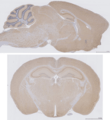

A coronal plane (also known as the frontal plane) is any vertical plane that divides the body into ventral and dorsal (belly and back) sections.

The coronal plane is an example of a longitudinal plane, because it is perpendicular to the transverse plane. For a human, the mid-coronal plane would transect a standing body into two halves (front and back, or anterior and posterior) in an imaginary line that cuts through both shoulders.